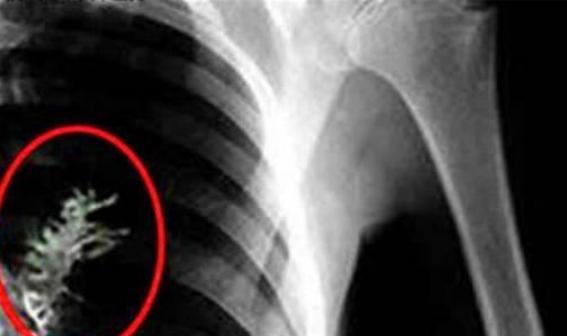

肺部怎么会长出树苗?这个问题听起来像是科幻电影里的情节,但在现实中还真发生过一件让人匪夷所思的事。 2009年,俄罗斯一名男子因为持续咳嗽和胸痛去医院检查,医生初步诊断可能是肺癌,准备手术切除肿瘤时,却在他的胸腔里发现了一个意想不到的东西。 手术台上,当医生切开患者的胸腔,原本以为会看到恶性肿瘤的画面,结果映入眼帘的竟然是几片嫩绿的叶子。 当时在场的医护人员都愣住了,谁也没想到人体里竟然能长出植物来。 经过仔细检查,确认这是一棵高度约5厘米的杉树苗,根系已经嵌入肺组织约2厘米,叶片还能进行微弱的光合作用。 这位患者名叫亚特尤姆·西多尔金,是一名普通园丁。 术后苏醒后,他回忆起2008年夏天的一场意外。 那天他正在修剪云杉树,突然刮起一阵大风,风里夹杂着树叶和种子直接灌进他的嘴里,当时他剧烈咳嗽了好几分钟。 本来以为没什么大事,没想到这粒小小的种子竟然在他的肺里安了家。 医生后来分析,西多尔金的肺部环境意外满足了种子萌发的条件。 他常年有花粉过敏,支气管黏膜存在轻微炎症,导致黏液分泌减少,种子没有被及时排出。 肺部37℃的恒温、95%的湿度,加上痰液中的微量营养,让这粒云杉种子在人体内慢慢扎了根。 这种情况发生的概率极低,但就是这么巧,各种条件都凑齐了。 类似的事情其实不止这一例。 2019年,巴西动物园有一只绿海龟因为误食芒果核,在食道里长出了3厘米的芒果苗;2021年,澳大利亚的研究人员在沙漠蜥蜴的胃中发现了萌发的草籽。 这些案例都证明,植物种子在恒温湿润的动物体内,确实存在非常规萌发的可能性。 西多尔金的经历也给医学界提了个醒。 他术前的咳嗽、胸痛症状被初步诊断为肺癌,差点就按癌症来治疗。 这说明医生在遇到类似症状时,还需要考虑呼吸道异物的可能性。 特别是那些有明确异物吸入史的患者,更要仔细排查,避免误诊。 手术后的西多尔金人生轨迹发生了改变。 他创立了一个叫“绿色呼吸”的组织,在西伯利亚发起防护林种植项目,截至2023年已经种了20万棵树。 同时他还为当地儿童提供免费的呼吸道检查,累计服务了1.2万人次。 本来想安安稳稳过日子的他,没想到因为这场意外,成了一名环保倡导者。 那棵从肺里取出的杉树苗现在被保存在莫斯科医学博物馆,旁边有西多尔金的手写寄语:“它曾让我恐惧,如今让我敬畏,每一粒种子,都是一个不屈的生命。” 这句话其实也反映了他心态的转变,从最初的恐惧到后来的敬畏,再到现在的行动,这场意外让他对生命有了新的理解。 这件事也引发了人们对人与自然关系的思考。 我们总以为人类是地球的主宰,却没想到一粒0.01克的种子能在人体里生长。 这其实提醒我们,人类和自然是相互依存的共同体,我们吸入自然的馈赠,呼出维持植物生长的二氧化碳,这种联系远比我们想象的要紧密。 西多尔金后来写了本自传叫《肺里的树》,2012年出版后在俄罗斯卖了50多万册。 他在书里写道:“生命总会找到自己的出路。” 这句话既是对那棵杉树苗的描述,也是对他自己人生的写照。 从疑似肺癌患者到环保卫士,他用自己的经历诠释了生命的韧性。 如此看来,这个看似离奇的医学案例,不仅为科学研究提供了独特的样本,更让我们重新审视人与自然的关系。 每一次意外的相遇,都可能成为改变认知的契机。 西多尔金的故事告诉我们,敬畏自然、守护生命,其实就是在守护我们自己的生存空间。 现在回头看,那棵在肺部生长的杉树苗,以一种不可思议的方式连接了人与自然。 它提醒我们,即使在最不可能的地方,生命也能绽放奇迹。 而人类要做的,就是学会与自然和谐共处,因为我们的呼吸,本就与这个世界紧密相连。